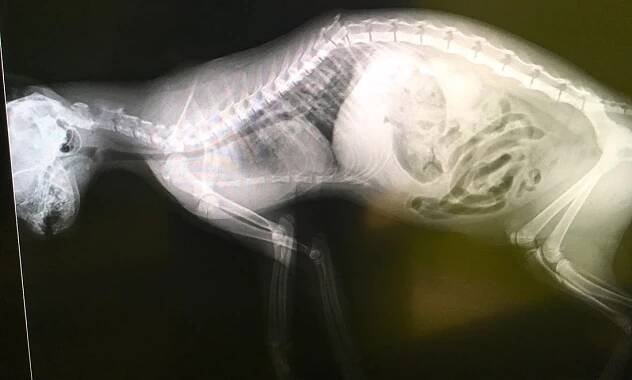

Bohužel velice smutní případ. Rentgen kočičky kterou majitele přinesli po napadení Rotweillerem který žil ve stejně domácnosti. Útok zlomil kočce celou páteř v polovině. Útok byl bohužel fatální.